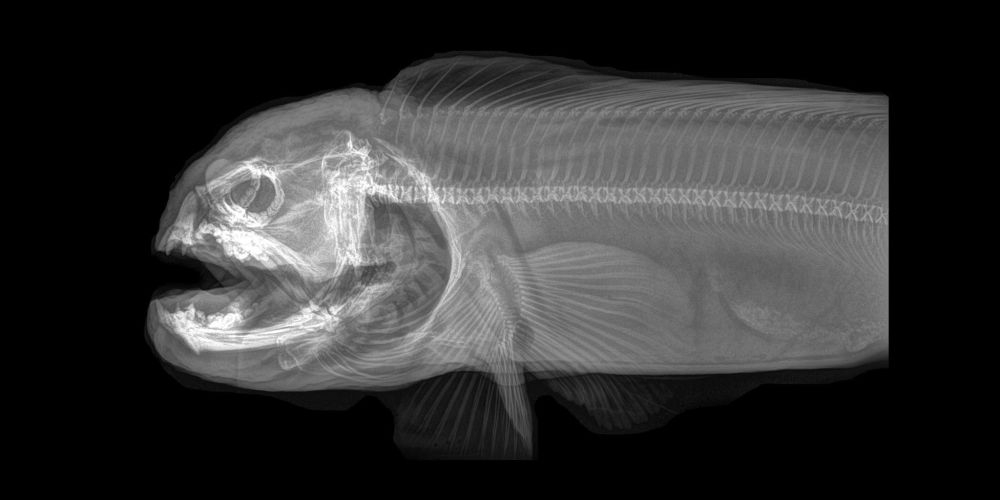

ABD'nin Oregon eyaletinde bulunan bir hayvanat bahçesi, hayvanların rutin sağlık kontrolleri sırasında çekilen X-Ray görüntülerini paylaştı.

Sağlık kontrolleri sırasında bazı hayvanlara röntgen çektiklerini söyleyen hayvanat bahçesi yetkilileri, bu yöntem sayesinde sağlık değerlendirmelerinin daha kolay yapıldığını ifade etti.